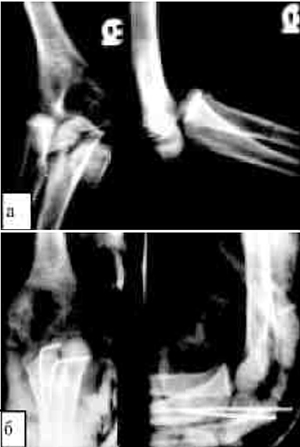

костнохрящевой фрагмент (рис. 2). |

Рис. 2. Заднемедиальный вывих обеих костей предплечья с

переломовывихом головки мыщелка плечевой кости: а) до репозиции; б)

после успешной одноразовой закрытой репозиции вывиха и переломовывиха

достигнуто восстановление конгруэнтности суставообразующих костей и

отломанного костнохрящевого фрагмента; в) через 6 лет после травмы:

полное анатомическое и функциональное восстановление взаиморасположения

и структуры костей локтевого сустава